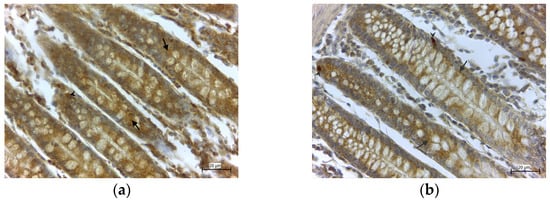

2.2. Immunohistochemical Detection of GPx4 and GPx8